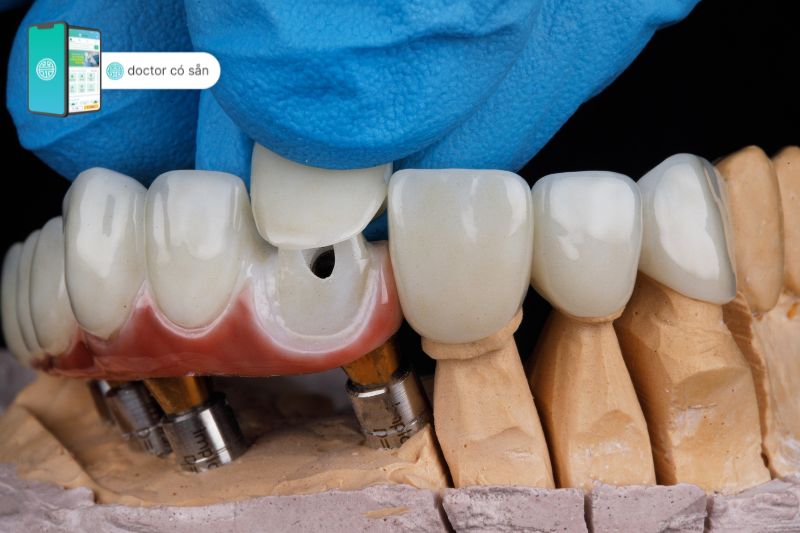

Theo định nghĩa thuật ngữ dán veneer trong nha khoa, đây là kỹ thuật sử dụng một lớp vật liệu cực kỳ mỏng chỉ khoảng 0,2 – 0,5mm, có màu sắc như răng thật, được dán vào phía trước của bề mặt răng bằng keo dán chuyên dụng sao cho ôm khít toàn thân răng một cách tự nhiên nhất, nhằm giúp cải thiện độ thẩm mỹ mặt trước của răng.

Thông thường, chất liệu để làm miếng dán veneer thường được làm từ các vật liệu cứng chắc, có độ bền cao, an toàn sinh học như là vật liệu sứ thủy tinh (mặt dán sứ) hoặc nhựa composite (mặt dán composite). Trong đó, mặt dán sứ veneer được sử dụng nhiều nhất do tính thẩm mỹ và độ cứng cao hơn nhựa composite.

- Miếng dán sứ veneer emax: Là một trong những dòng mặt dán sứ veneer cao cấp, được làm từ sứ thủy tinh lithium disilicate do sở hữu màu trắng đục và khả năng khuếch tán ánh sáng nên nhìn giống như răng thật. Loại dán veneer này hạn chế tối thiểu men răng cần mài, chỉ cần mài một lớp men mỏng từ 0,3 – 0,5mm là có thể cố định được miếng dán và vừa vặn vị trí cần phục hình.

- Trang thiết bị y tế hiện đại: Hỗ trợ nha sĩ trong việc thực hiện dán veneer, Nha khoa 2000 sử dụng trang thiết bị và công nghệ tiên tiến nhất để đảm bảo veneer có chất lượng cao và vừa vặn hoàn hảo.

- Nha sĩ sẽ lấy dấu bề mặt răng đã mài gửi đến labo để thực hiện dán veneer.

- Trước khi dán veneer, nha sĩ sẽ kiểm tra độ vừa vặn, hình dạng, màu sắc của mặt dán.

- Gắn mặt dán veneer lên răng, sử dụng xi măng nha khoa chuyên dụng để dán dính veneer với răng thật.

- Kiểm tra khớp cắn xem tương thích chưa, cuối cùng là đánh bóng mặt dán veneer hoàn tất.